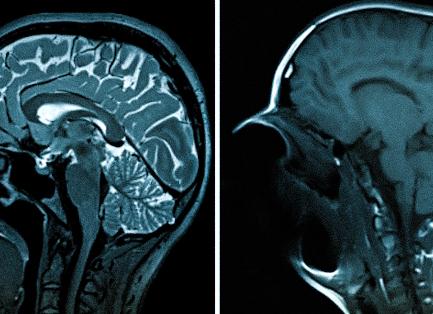

В настоящее время большинство заболеваний значительно молодеют и болезни женской половой системы не исключение. Благодаря современным методам диагностики, таким как УЗИ, стала доступна возможность заранее выявить заболевание и полностью избавиться от него. Исследование с помощью эхографии информативно, при этом безболезненно и не имеет противопоказаний, но эндометриоз на УЗИ выявить достаточно сложно. Для точного выявления патологии прибегают к лапораскопии и гистероскопии.